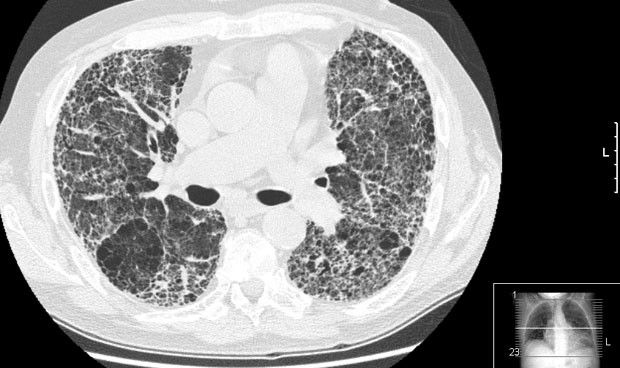

No hay otras manifestaciones propias de la enfermedad, aunque pueden estar presentes las debidas a la asociación de comorbilidades como hipertensión pulmonar, enfisema, síndrome de apneas hipoapneas del sueño, cáncer de pulmón o RGE1,2. Los médicos de familia estamos acostumbrados a diagnosticar y tratar enfermedades pulmonares crónicas como la EPOC y el asma debido a su alta prevalencia en nuestras consultas, pero es importante realizar un diagnóstico diferencial ante pacientes con disnea que tras descartar estas 2 enfermedades obstructivas pueden presentar otras enfermedades respiratorias menos frecuentes o raras. Se define como un rápido deterioro de la enfermedad en ausencia de infección respiratoria, insuficiencia cardíaca, embolismo pulmonar o cualquier otra causa identificable.

La sustitución cicatricial del tejido normal de pulmón provoca disminución irreversible de la capacidad de difusión de oxígeno (oxigenación).[3] Por otra parte, la disminución de la distensibilidad pulmonar por fibrosis conforma una enfermedad pulmonar restrictiva. La genética puede desempeñar un papel en la causa de la fibrosis pulmonar.[19] Si más de un miembro de una familia tiene fibrosis pulmonar, la enfermedad se llama fibrosis pulmonar familiar.[19] La fibrosis pulmonar puede no tener causa conocida, en cuyo caso se denomina fibrosis pulmonar idiopática, o puede ser causada por un gran número de variables, en cuyo caso suele remitir al eliminar el factor desencadenante.

¿Y cuáles son los principales síntomas de la fibrosis pulmonar idiopática? Según este neumólogo, los primeros signos son la fatiga y ahogo al realizar un esfuerzo (disnea), la tos seca e irritativa, los cambios en las uñas de manos y pies o dedos de palillo de tambor (acropaquia), los sonidos crepitantes al respirar (similares al ruido que produce el velcro) y, por último, el pulmón en panel de abeja, es decir, cuando el órgano pierde su forma habitual y adopta una estructura parecida a un panal. Este acto también ha contado con la participación de la Asociación de Familiares y Enfermos de Fibrosis Pulmonar Idiopática (Afefpi) y la Federación Española de Enfermedades Raras (Feder), así como la colaboración de los laboratorios Boehringer.